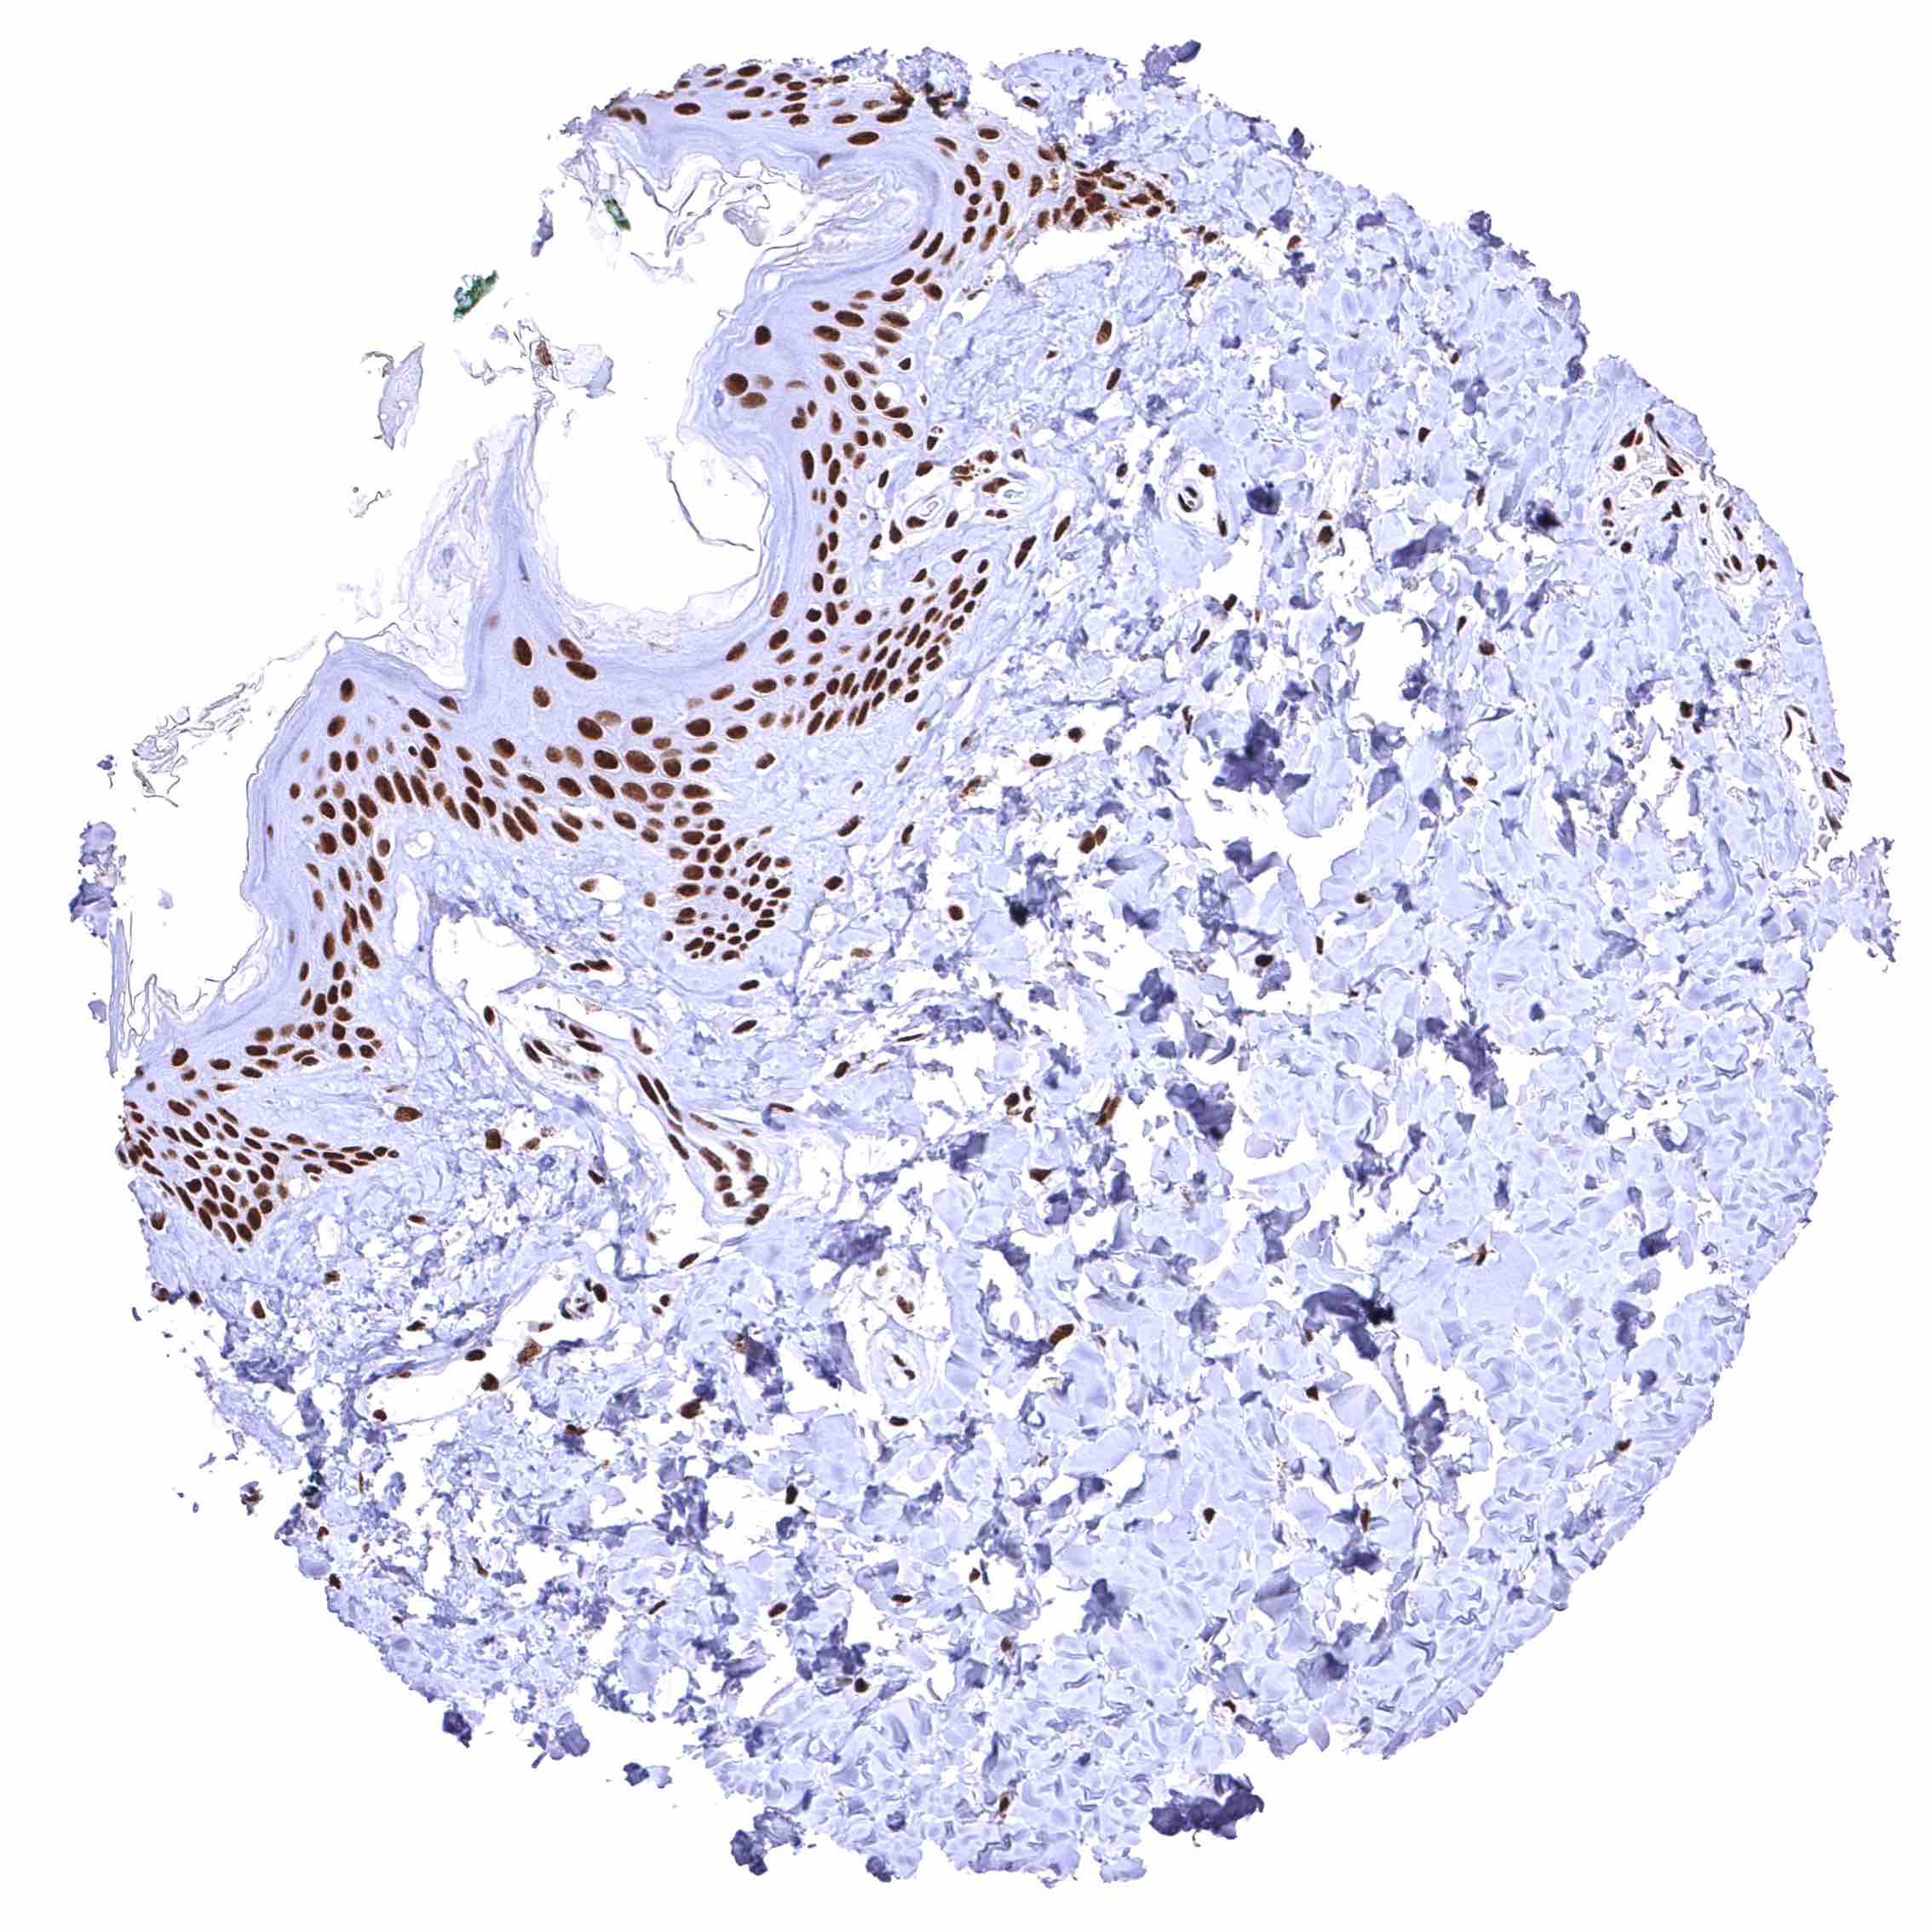

Skin – Strong nuclear BRD4 staining of squamous epithelial cells.

Skin, hairfollicel and sebaceous glands – Moderate to strong BRD4 staining of sebaceous gland cells. Nuclear BRD4 staining is somewhat stronger in associated hair follicles cells.